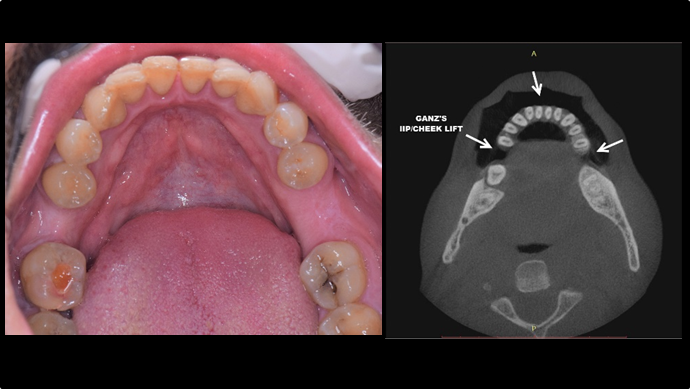

Clinical case: EImmediate implant placement & loading of #35 extraction socket with defect

- Courtesy of Dr. Kwang Bum Park, Korea -